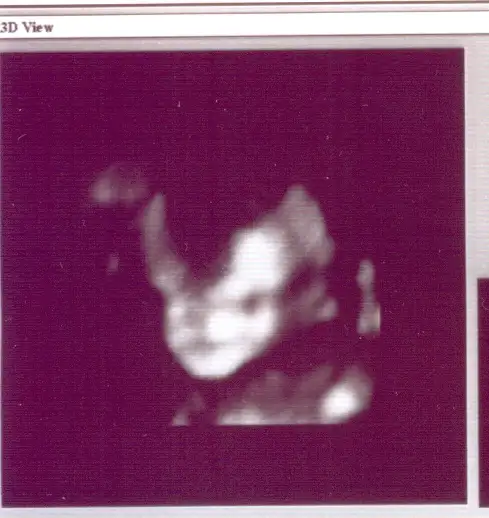

kızlar bu benim oğluşumun yüzü. ne kadar da belirginleşmiş artık degil mi?

maşallah yakında kime benziyor diye tahminlere başlarsınız artık

oo tahminler simdiden var. kayınvalıdem esıme annemde kardesıme benzetıyor. herkez kendı aılesıne benzesın ıstıyor anlayacagın :)

ama özellikle son aylarda yüzünün net bir resmini yakalamak gerek. insan o resimlerin gerçeğe ne kadar yakın olduğunu doğumdan sonra anlıyor.